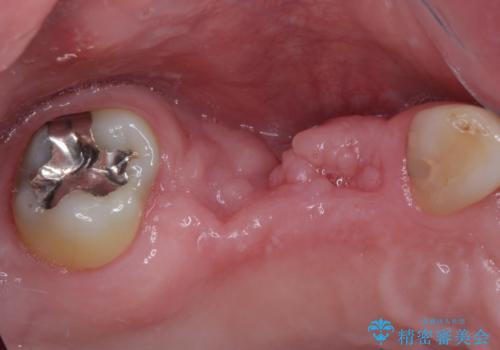

- 地元ではなかなかインプラント治療を行ってくださる医院がないとのことで、転勤で東京にいる期間に治療を行いたいとのことで来院された患者様です。

上顎は左右ともに骨が少ない状態であり、特殊なドリルを用いた歯槽骨の拡大や自家骨挙上などを行いながらインプラントを埋入していくこととしました。

右下の銀歯も気になるとのことで、インプラント治療と並行してオールセラミックによるブリッジ補綴治療も行うこととしました。